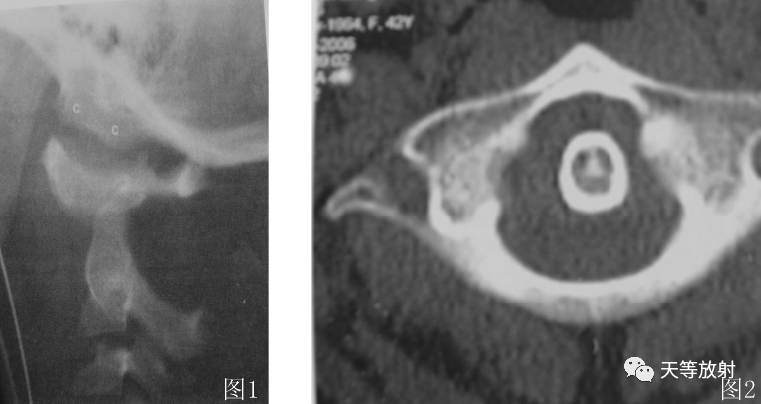

图 1 环枕和环枢关节脱位,3. 5 岁儿童侧位 X 线片,显示颅基底相对 C1 向头侧脱位,且 C1 相对 C2 前脱位。环枕关节间隙增宽。枕髁( 白 c) 从枕窝横移位。C1相对 C2 前移动致环齿前间隙( AADI) 增宽 > 4mm。

图 2 CT 横断面图像示: 环椎前弓向前错位,造成环枢椎脱位。